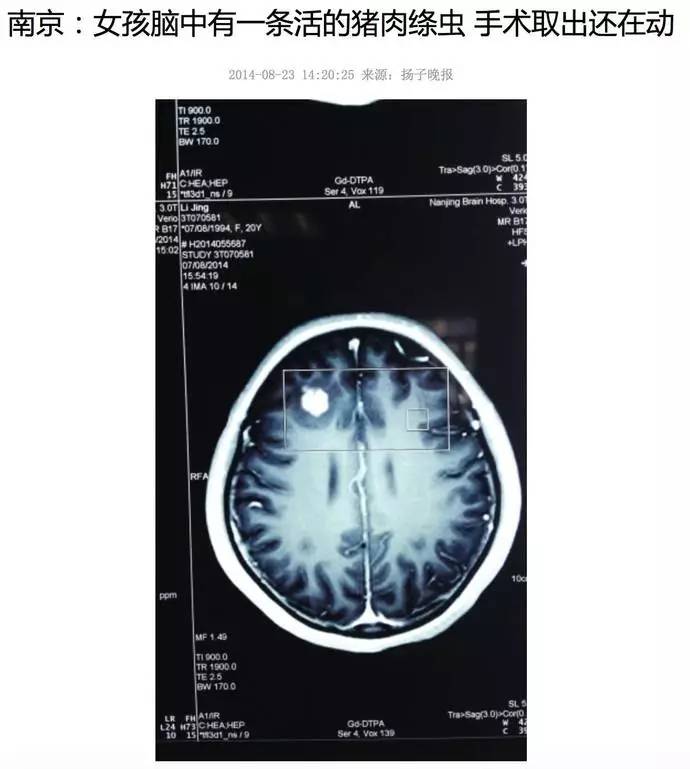

猪肉绦虫有多可怕

猪肉绦虫是猪肉里面最主要的寄生虫,属于人畜共患的寄生虫,成虫在人体内寿命可达25年以上,这种寄生虫极其可怕!会通过血管进入你的皮肤、进入你的身体各处甚至进入你的脑子!然后就可能癫痫犯病,脑干受损成为傻子,进入眼睛,双目失明!